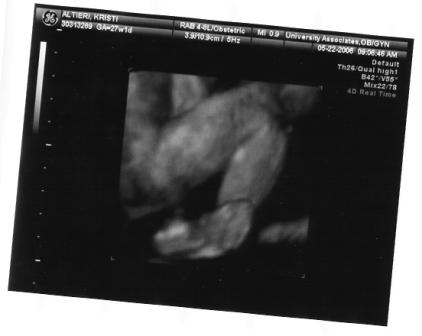

I'm back and everything went great. The cyst is barley visible and the doc said she might not need anything done after she is born. I am so happy I can't even explain. I go back in a month for another sono/check-up. I was surprised that they did a 3d sono I totally didn't expect it. She is pushing up against the placenta so there isn't a clear shot of her face.

here you go!

the first one looks great!! what a cutie. so glad all is going well.